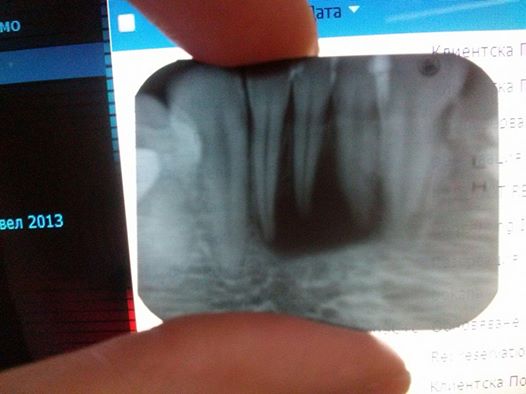

Имам дъщеря на 9 години и от малка имаме проблем с кариеса. Още на 4-5 годишна възраст ни направиха пломби почти на всички задни зъби. Много бързо и се получава кариес и незнам защо. Вярно, че в началото устната й хигиена не беше както трябва, но вече си мие зъбите постоянно и пак на преглед през 6 месеца ни намират малки кариесчета. Като попитах лекуващия лекар, каква може да е причината, ми каза че най-вероятно е предрасположена към кариес. Какво може да означава това? Трябва ли да си направим изследвания за калций или някое друго изследване, за да разберем причината?